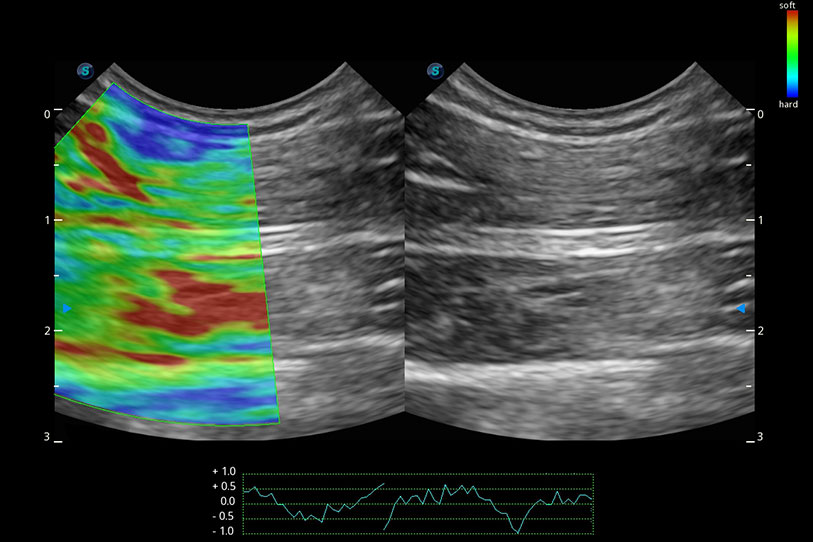

操作簡(jiǎn)便,無(wú)需高頻度外力作用即可真實(shí)反映組織的形變,快速評(píng)估腫瘤良惡性。

實(shí)時(shí)用顏色表示心肌組織運(yùn)動(dòng),觀察和定量組織的運(yùn)動(dòng)情況,對(duì)快速檢測(cè)與評(píng)估心肌的灌注和活性、電傳導(dǎo)及心肌收縮和舒張功能等均能提供重要的診斷信息。